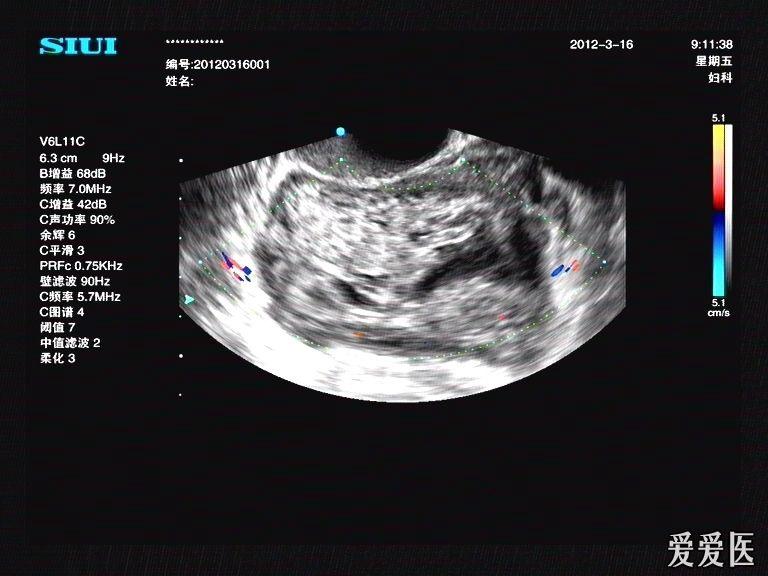

宫外孕破裂型包块

图片尺寸768x576